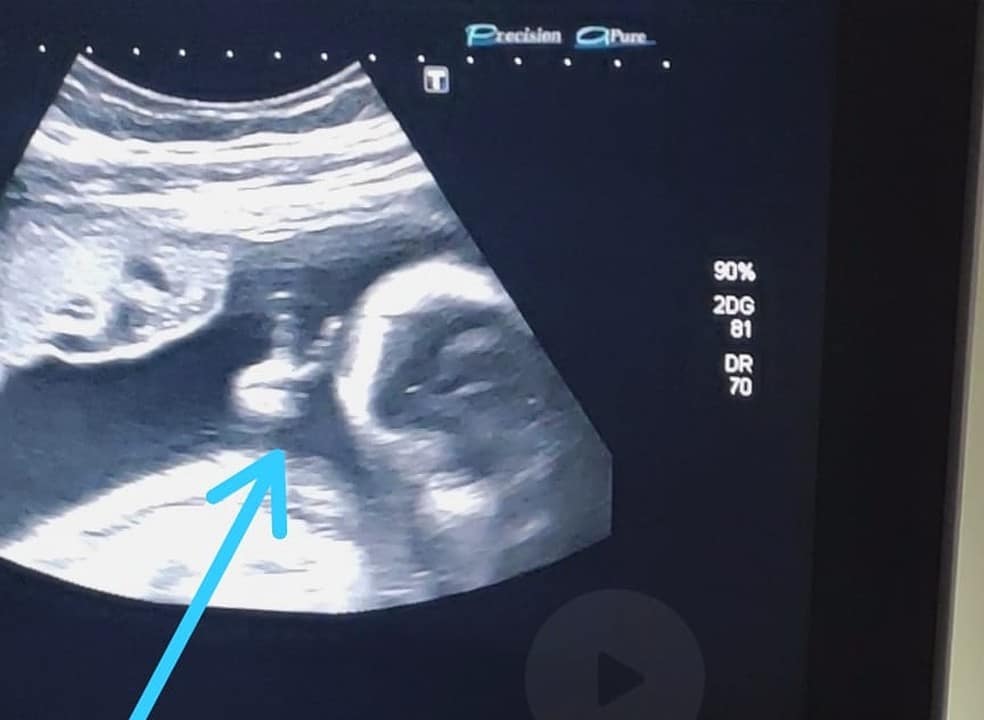

O rapaz, que mora no Guarujá, litoral de São Paulo, estava acompanhando o exame de ultrassonografia de sexto mês do seu primeiro filho, quando percebeu que o bebê estava fazendo um ‘V de vitória’ com a mãozinha dentro do útero. O Ele encarou o gesto do bebê como um sinal divino, pois enfrenta um câncer raro no baço.

Ele falou ainda sobre a surpresa e a aemoção que sentiu ao ver o filho Davi fazendo um sinal de ‘V’ com uma das mãozinhas. “Até a médica falou: ‘olha, ele fez o sinalzinho de vitória com a mão’. Eu fiquei sem acreditar”, afirma. Para Felipe, o gesto do filho é um sinal divino de que vai conseguir superar o tratamento e vencer a doença.